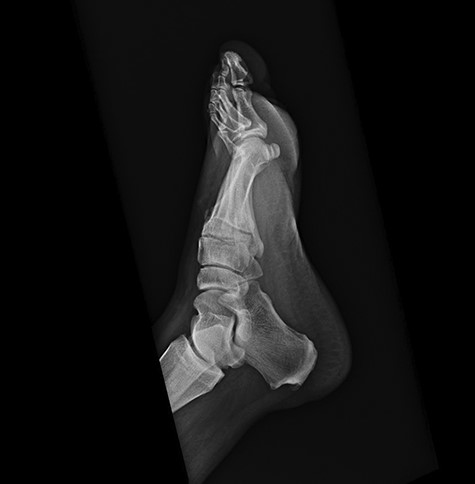

Repeat lateral X-ray views of the foot, 2 months later, showed ‘interval appearance of large soft tissue mass, plantar to the phalanges’. The differential diagnostic consideration by the imaging studies included ‘phlegmon, abscess, hematoma, or less likely a rapidly growing neoplasm’.

Approximately 2 months following surgical excision of the tumor, the patient presented with a significantly enlarged and painful recurrence of the mass (Fig. 5). Repeat X-rays of the foot showed ‘interval large soft tissue mass’ (Fig. 6). Nuclear three-phase bone scan was ‘suspicious for osteomyelitis or tumor involvement of bone’.